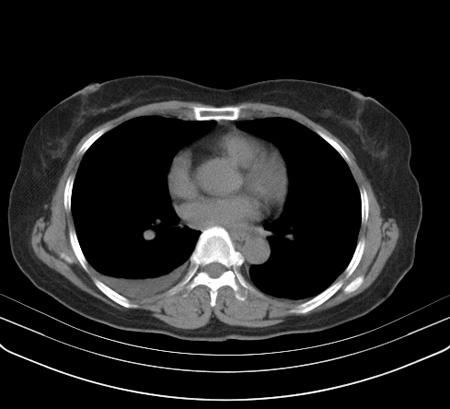

以下是引用余辉在2009-2-19 20:10:00的发言:[br]多考虑急性感染性病变,右中叶尚可见多枚小斑片状影,多为化脓性肺炎,双侧胸腔积液

以下是引用随光逐影在2009-2-19 20:33:00的发言:[br]1)考虑右肺炎症;建议抗炎治疗后复查。2)双侧胸腔积液(以右侧为甚)。

以下是引用花凤凰在2009-2-19 20:46:00的发言:[br]病人有发热,胸痛急性起病,主要病变位于右肺中叶外侧段,呈楔行改变,位于外带胸膜下,考虑为肺梗塞可能!!!!!!!!!!!!!!!!!!!!!!!!!!!!!!!!!!!